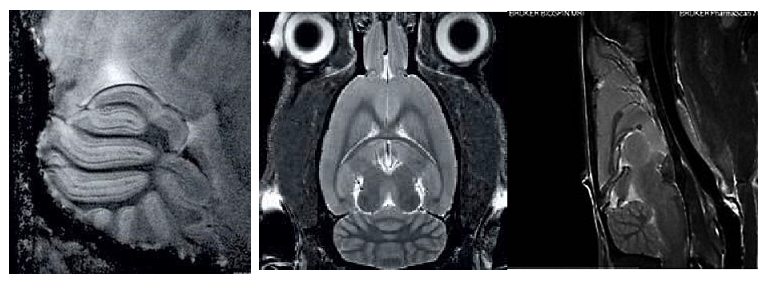

1、高分辨率神經(jīng)解剖結(jié)構(gòu)

布魯克結(jié)合超高磁場(chǎng),先進(jìn)的相陣控線圈和譜儀技術(shù)提供完美品質(zhì)的結(jié)構(gòu)形態(tài)成像。超高空間分辨率可以顯示精細(xì)的顯微組織結(jié)構(gòu)。領(lǐng)先的磁共振成像技術(shù)在超高磁場(chǎng)下提供完美的對(duì)比度。

磁共振成像低溫探頭增加150%的靈敏度,清晰顯示小鼠腦部細(xì)胞層狀結(jié)構(gòu)(小腦的顆粒層和浦肯雅細(xì)胞層),空間分辨率達(dá)到 50μm: